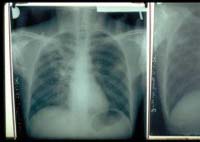

Por ser uma doença que, anualmente, mata quase 2 milhões de pessoas, caracterizando-se por atingir os pulmões, o tratamento da tuberculose deve ser realizado por um período de seis meses. Isso porque, caso não seja tratada de forma adequada, o Bacilo de Koch pode voltar a atacar os pulmões, causando resistência à medicação.